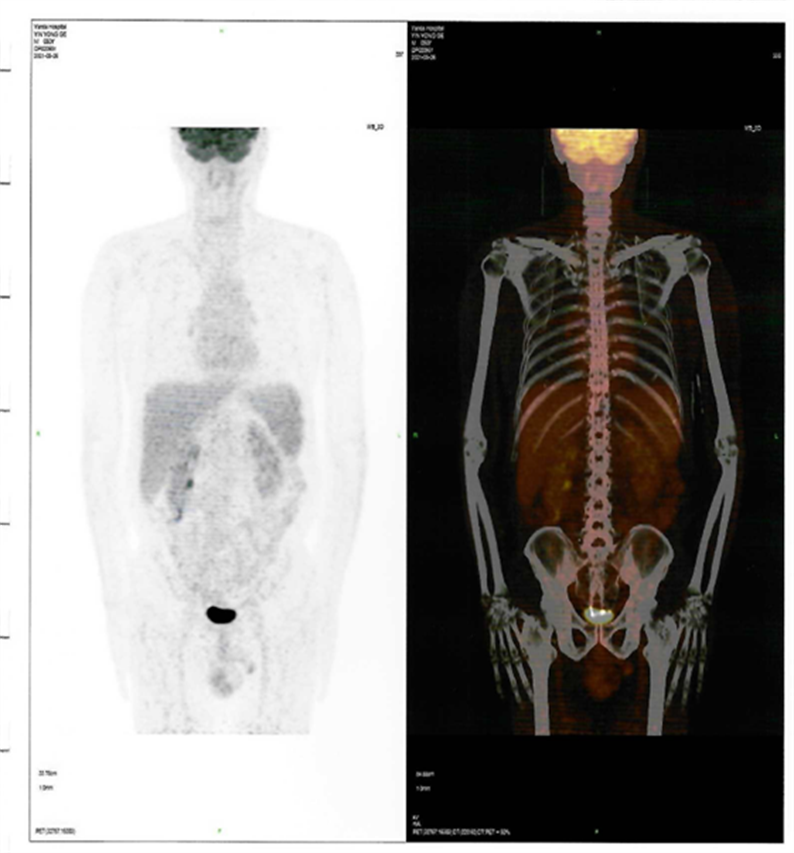

近日,燕達(dá)陸道培醫(yī)院血液科二病區(qū)傳來(lái)好消息,一位罹患T細(xì)胞淋巴瘤前期在美國(guó)治療復(fù)發(fā)的患者,428日,在我院回輸CD7 CAR-T細(xì)胞,526日經(jīng)PET-CT檢查,顯示CR(完全緩解)。

患者CAR-T 前后PET-CT檢查結(jié)果對(duì)比圖

CAR-T治療前

CAR-T治療后30

2021412日,患者來(lái)到燕達(dá)陸道培醫(yī)院,希望借助我院的CD7 CAR –T臨床試驗(yàn)項(xiàng)目獲得一線生機(jī)?;颊叱跞朐簳r(shí)PET-CT檢查提示:腫瘤細(xì)胞累及多處腸系膜和腹部肌肉軟組織;骨髓未累及。

回輸后一度出現(xiàn)了一級(jí)CRS反應(yīng),癥狀可控,526日,回輸后+28天復(fù)查PET-CT顯示CR(完全緩解)。預(yù)祝黃山先生接下來(lái)的治療一切順利!